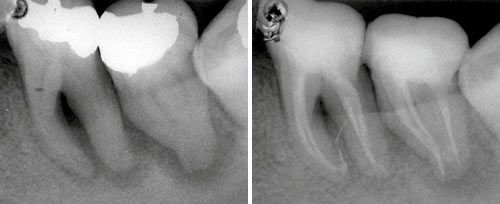

Periimplantitis Treatment

Courtesy of: Ilay Maden Ph.D., M.Sc.

Laser source: Er:YAG (2940 nm)